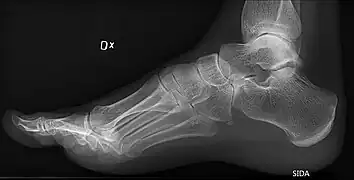

High arch in foot of a person with a hereditary neuropathy

Pes cavus, also known as high arch, is a human foot type in which the sole of the foot is distinctly hollow when bearing weight. That is, there is a fixed plantar flexion of the foot. A high arch is the opposite of a flat foot and is somewhat less common.

On weightbearing projectional radiography, pes cavus can be diagnosed and graded by several features, the most important being medial peritalar subluxation, increased calcaneal pitch (variable) and abnormal talar-1st metatarsal angle (Meary's angle).[14] Medial peritalar subluxation can be demonstrated by a medially rotated talonavicular coverage angle.[14]